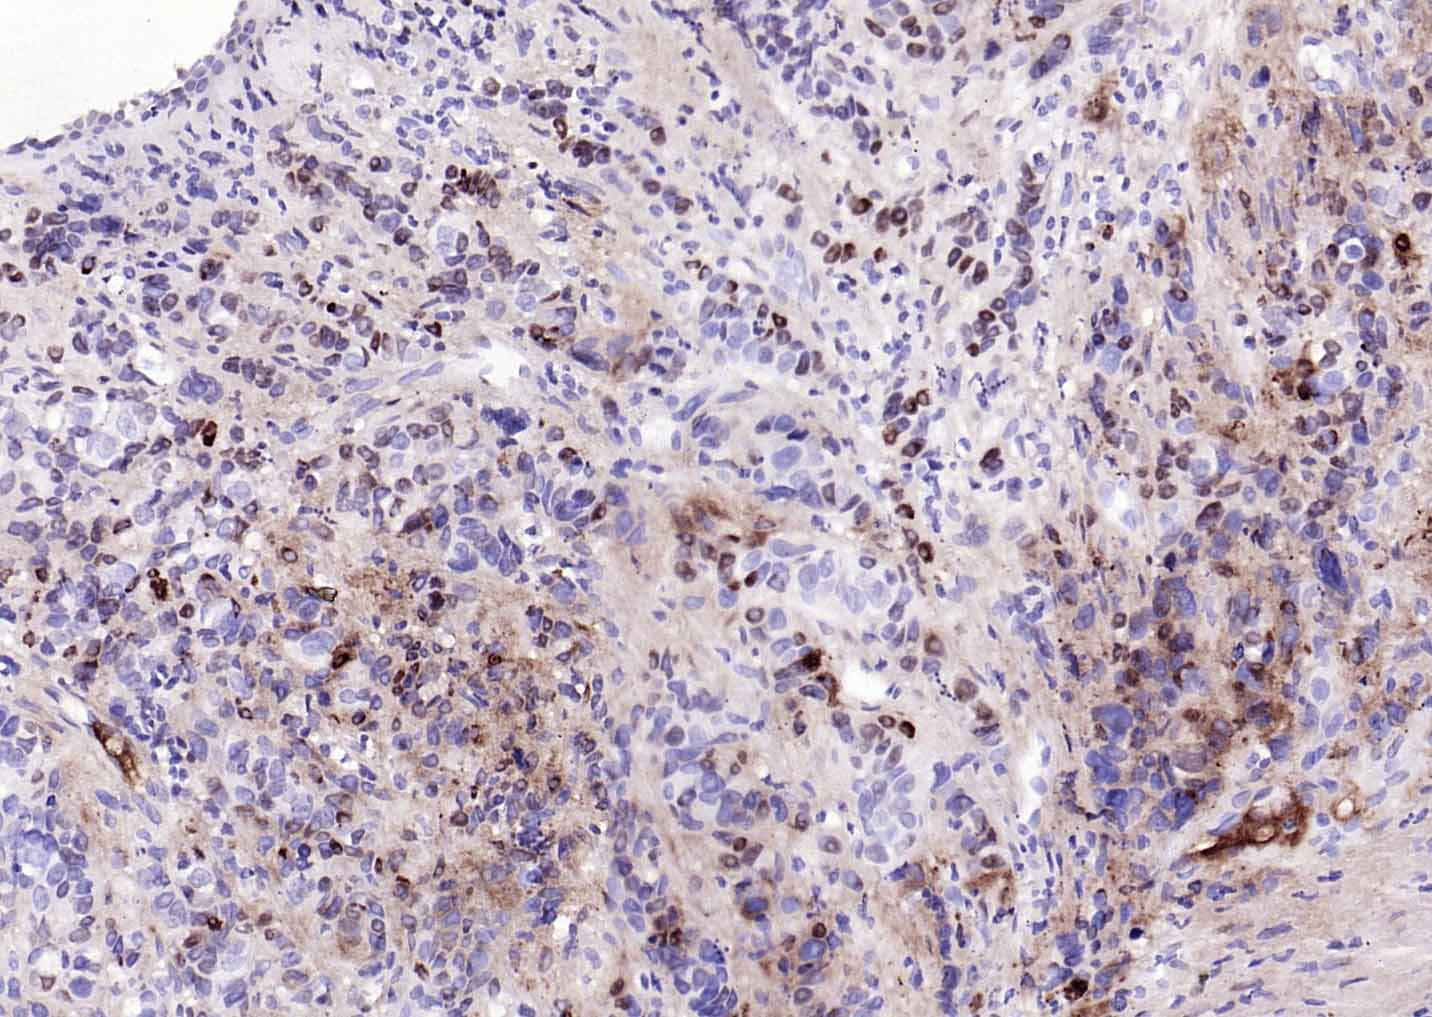

| 产品应用 | WB=1:500-2000, IHC-P=1:50-200, IHC-F=1:50-200, IF=1:100-500, Flow-Cyt=1:50-200 Not yet tested in other applications. |

| {IHC-P} | {1:50-200} |